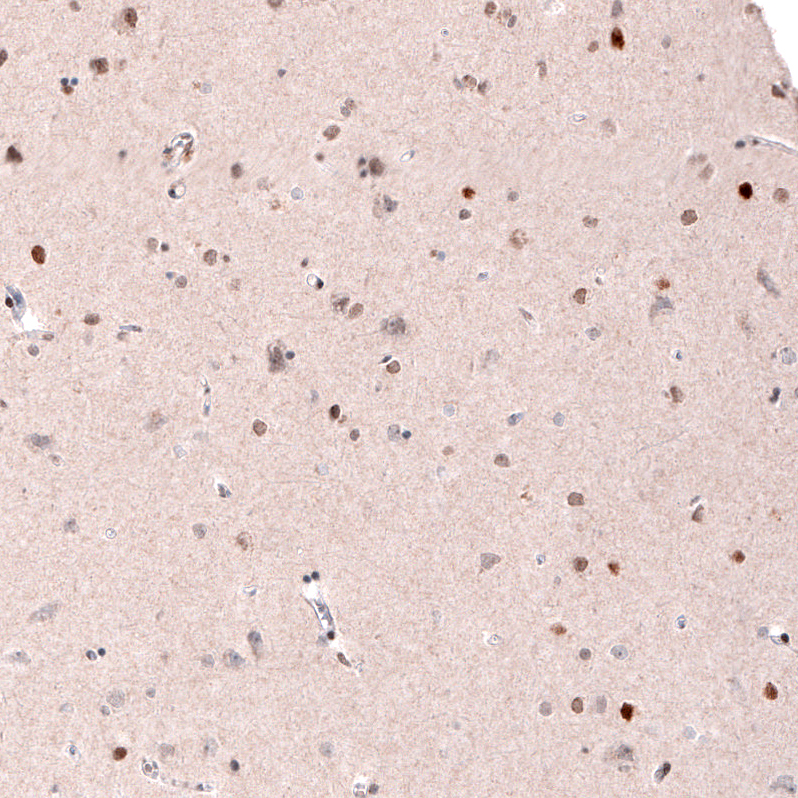

Immunohistochemical staining of human cerebral cortex shows moderate to strong nuclear positivity in a subset of neurons.